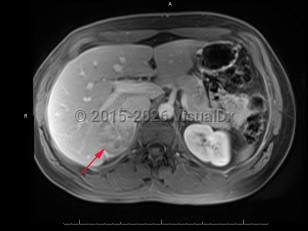

An adrenocortical carcinoma is a rare (1 case per 1 million adults) malignant tumor of the adrenal cortex. The tumor is typically unilateral and may have an irregular shape. Adrenal carcinomas may be found incidentally on imaging or may be identified after a patient shows signs of endocrine dysfunction, such as hypercortisolism or virilization. About half of adrenal carcinomas do not produce hormones, while the other half produce any combination of the normal adrenal cortical hormones. Adrenal carcinomas have a bimodal epidemiology. They are most common in children aged younger than 5 years and in middle-aged adults. Syndromes such as multiple endocrine neoplasia type 1 are uncommonly the cause of adrenal carcinoma.